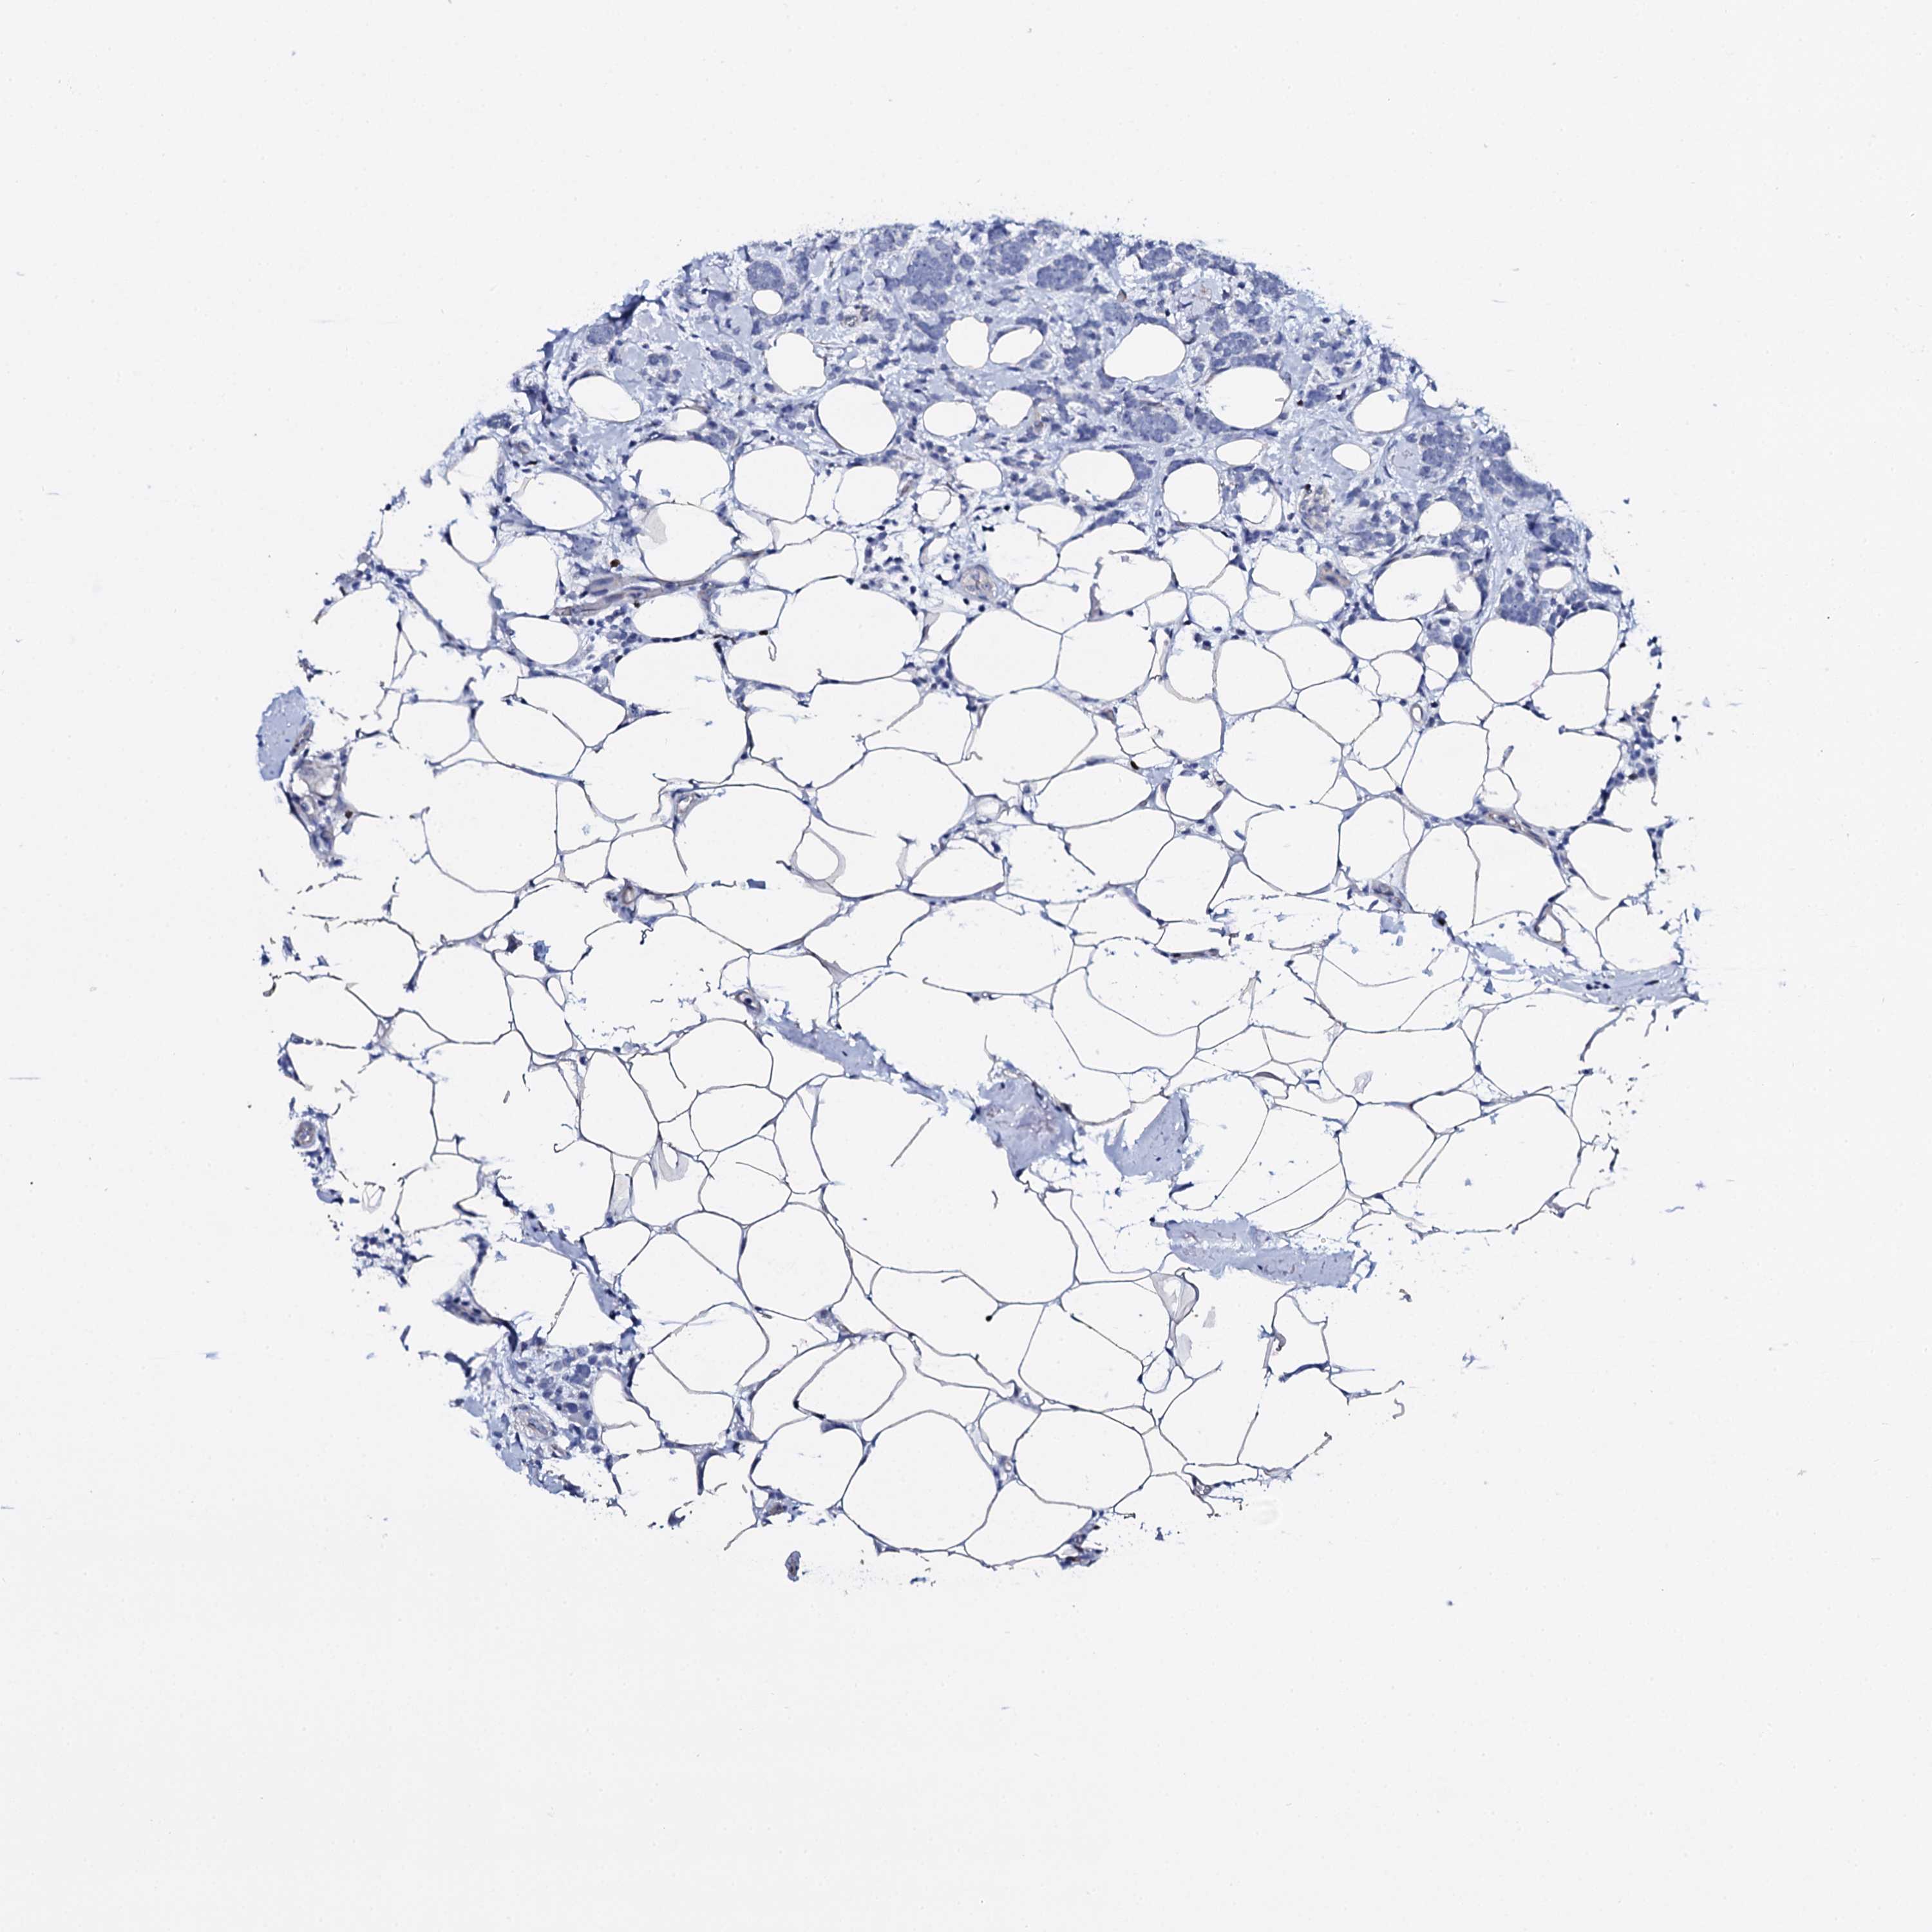

CANCER BREAST CANCER Show tissue menu

BRCA TCGA BRCA VALIDATION PROTEIN EXPRESSION

Breast cancer

Human cancer

Breast invasive carcinoma